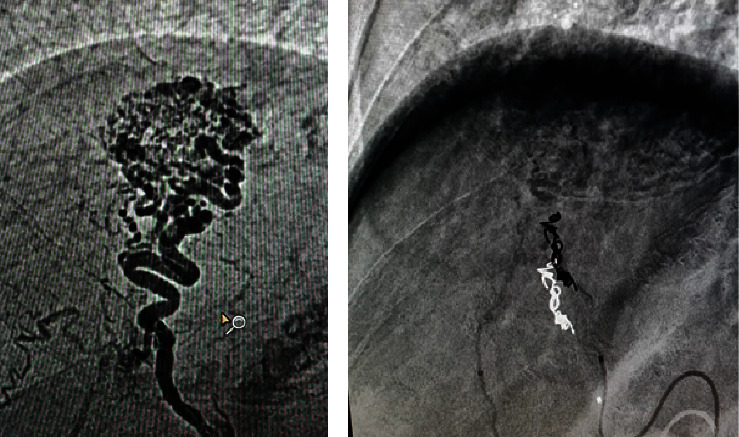

Hereditary hemorrhagic telangiectasia (HHT), also known as Rendu-Osler-Weber syndrome, is a vascular disorder of autosomal dominant etiology. The hallmark clinical feature is the presence of recurrent episodes of epistaxis in patients with vascular malformations and a tendency to bleed. We present the case of a 71-year-old woman who presented to the emergency department with upper gastrointestinal bleeding caused by esophageal varices, in conjunction with gastric angiodysplasias. The presence of oronasopharyngeal telangiectasias and hepatomegaly raised suspicion of HHT. The diagnostic workup confirmed the presence of angiodysplasia in the gastric region, portal arteriovenous malformation, and a pulmonary shunt.

遗传性出血性毛细血管扩张症(HHT)又称伦杜-奥斯勒-韦伯综合征,是一种常染色体显性遗传的血管疾病。其主要临床特征是患者反复发作鼻衄,伴有血管畸形和出血倾向。本病例是一名 71 岁的妇女,因食管静脉曲张并发胃血管增生症引起上消化道出血而到急诊科就诊。口咽部毛细血管扩张和肝脏肿大使她怀疑自己患有 HHT。诊断检查证实了胃区血管增生、门静脉畸形和肺分流。